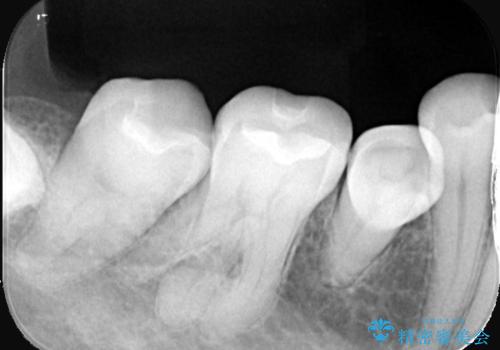

- 主訴:口を開けると所々入っている銀の詰め物が目立つので白い物にやり替えたい。

下顎大臼歯部に入っている保険適用のメタルインレーを、適合性と審美性の良いセラミックインレーでのやり替えとなりました。

メタルインレーを除去した際、古い裏層材やカリエスは除去し新たにCR裏層しています。

セラミックインレーセット時はラバーダム防湿を行っています。